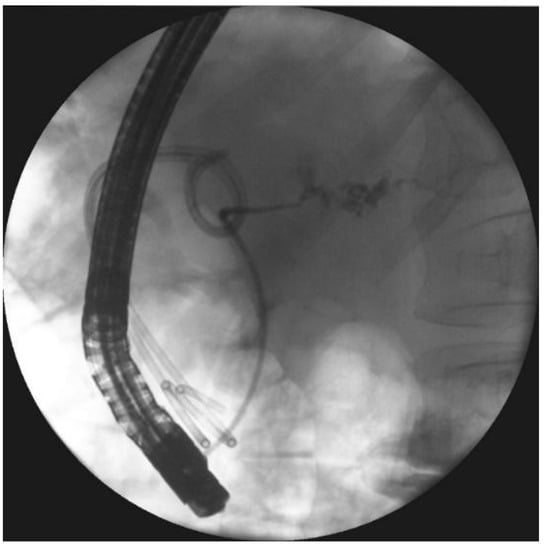

- Smoczyński, M.; Jagielski, M.; Siepsiak, M.; Adrych, K. Endoscopic necrosectomy through the major duodenal papilla under fluoroscopy imaging. Arch. Med. Sci. 2018, 14, 470–474. [Google Scholar] [CrossRef] [PubMed]

| Passive transpapillary drainage | The insertion endoscopic pancreatic stent to pancreatic duct through duodenal papilla. |

| Active transpapillary drainage | Endoscopic insertion pancreatic endoprosthesis as well as nasal drain to pancreatic duct through duodenal papilla. |

| Endoscopic necrosectomy under fluoroscopic guidance (endoscopic debridement) | Procedure that enable to remove necrotic tissues from necrotic cavity through transmural fistula under fluoroscopy with use of various types of endoscopic tools. Indication for endoscopic debridement is WOPN containing poorly-liquefied necrotic tissues. |